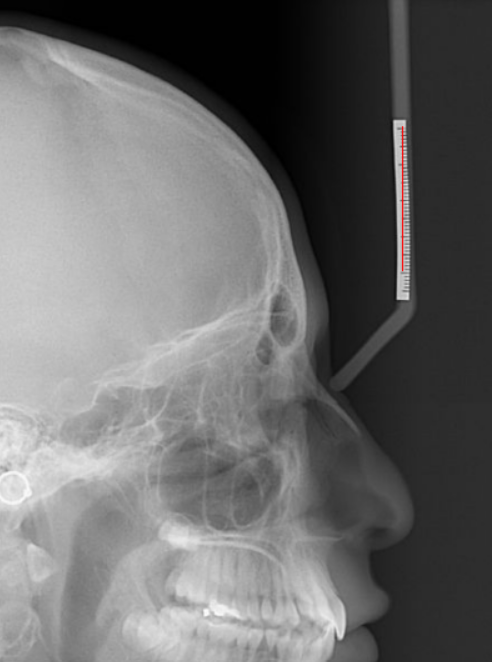

Sur l'exemple que nous allons voir, nous allons saisir une valeur de 40 mm (suivant la taille de votre étalomètre présent sur votre cliché).

Après avoir saisie la valeur de 40, le logiciel attend que vous traciez une droite de cette valeur.